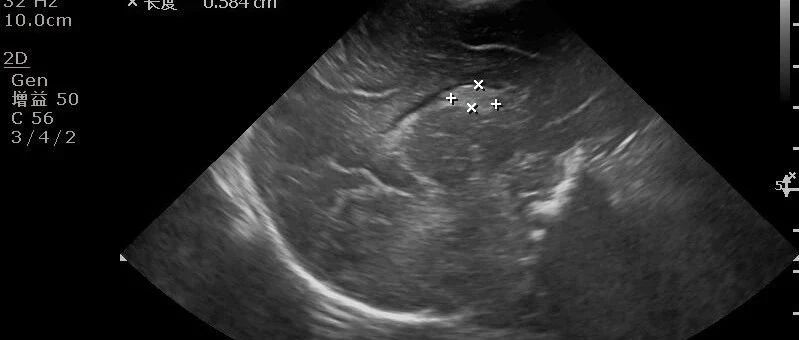

经典病例:遇到这样的胃窦癌,你能确诊吗? 丁香园超声时间 · 公众号 · 医学 · 1 年前 · |